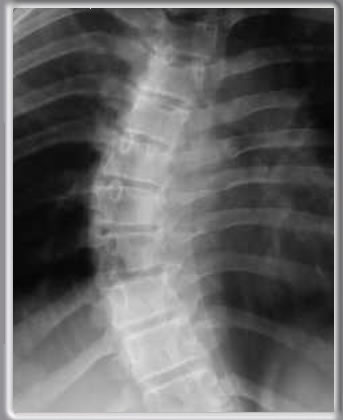

ANGULO DE COBB